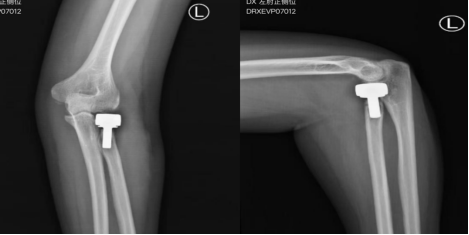

一次意外事故,张先生(化名)的左肘部遭遇了“毁灭性”打击——摔倒瞬间,肘部受力,剧烈的疼痛让他当场无法活动手臂。异地就诊,张先生被确诊“桡骨小头粉碎性骨折”,随后紧急实施手术。术后1个半月复查时,张先生出现严重肘关节伸屈和旋转功能障碍,X线发现钢板固定的骨折发生明显的移位。

在外地的张先生迅速返回青岛,来到青岛市立医院东院骨关节外科副主任医师申友亮的门诊就诊。接诊后,申友亮敏锐察觉到病情的复杂性——陈旧性桡骨小头粉碎性骨折合并肘关节僵硬,不仅骨折端移位明显,长期的制动还导致周围软组织严重粘连、挛缩,手术难度远超常规骨折修复。

经与患者及家属的充分沟通,团队确定了“桡骨小头置换术+肘关节松解术”的一站式手术方案——既解决桡骨头的结构缺损问题,又同步解除软组织粘连,实现“修复+功能恢复”双重目标。

手术过程历时1.5小时,主刀医生申友亮始终保持着“零误差”的操作精度——微创切口减少了术中出血,取出破碎的桡骨小头,安放人工桡骨小头假体。精准的假体匹配和松解操作避免了神经血管损伤,手术过程顺利。